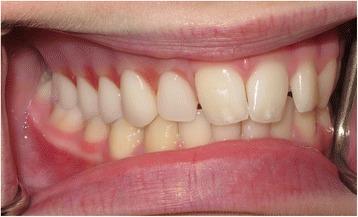

This report details the use of zygomatic oncology osseointegrated implants to support and retain a maxillary obturator in a 13-year-old male patient who underwent a right-sided hemi-maxillectomy (Brown Class 2b) (Brown and Shaw, Lancet Oncol 11:1001-8, 2010) for a myxoid spindle cell carcinoma. At the time of maxillary resection, two zygomatic oncology implants were inserted into the right zygomatic body and subsequently utilised to provide in-defect support and retention for a bar-retained maxillary acrylic obturator prosthesis, which restored the patient's aesthetics and function to a very high level. Close follow-up over 2 years demonstrated ongoing excellent function and disease control with no deleterious effects on facial or dento-alveolar growth clinically. This is the first clinical report of its kind in the published literature detailing the use of a zygomatic implant-retained obturator in a paediatric patient.

本报告详细介绍了在一名13岁男性患者中使用颧骨肿瘤骨整合种植体来支撑和固定上颌阻塞器的情况。该患者因黏液样梭形细胞癌接受了右侧半上颌骨切除术(Brown 2b级)(Brown和Shaw,《柳叶刀·肿瘤学》11:1001 - 8,2010年)。在上颌骨切除时,将两枚颧骨肿瘤种植体植入右侧颧骨体,随后用于为杆式固定的上颌丙烯酸阻塞器假体提供缺损内支撑和固定,该假体将患者的美观和功能恢复到了很高水平。超过2年的密切随访显示,功能持续良好且疾病得到控制,临床上对面部或牙牙槽骨生长无不良影响。这是已发表文献中首例详细介绍在儿科患者中使用颧骨种植体固定阻塞器的临床报告。